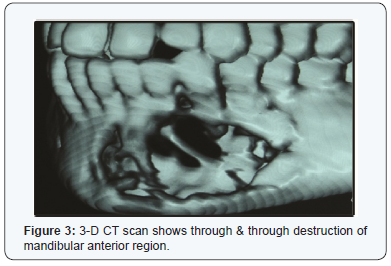

Computerized Tomograph (CT) Figure 3 showed a destruction of the alveolar and basilar bones of anterior region of the mandible extending from tooth 35 to 43.